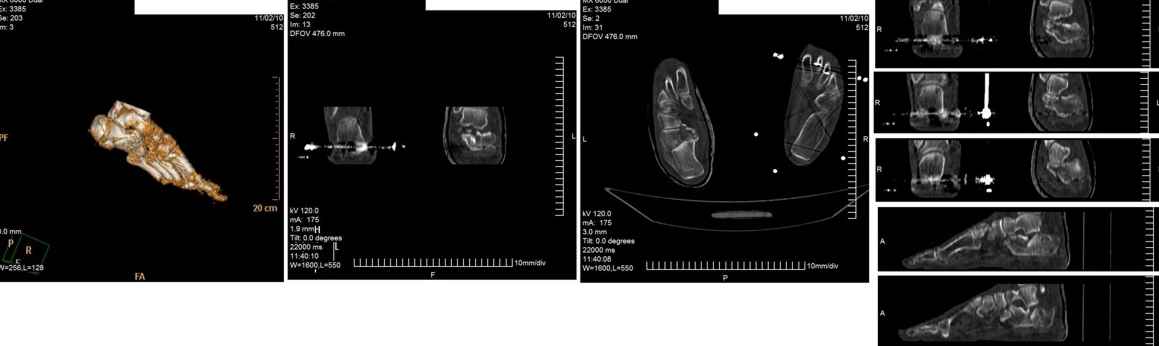

Мужчина, 47 лет. Диагноз: Кататравма (26.10.10г. падение с высоты 2го этажа).

Открытый оскольчатый внутрисуставной перелом дистального метаэпифиза лучевой кости, перелом шиловидного отростка локтевой кости левого предплечья со смещением отломков, закрытый оскольчатый внутрисуставной перелом дистального метаэпифиза лучевой кости, перелом шиловидного отростка локтевой кости правого предплечья со смещением отломков. Закрытый оскольчатый внутрисуставной перелом левой пяточной кости, закрытый оскольчатый внутрисуставной перелом дистального метаэпифиза обеих костей правой голени со смещением отломков, закрытый компрессионно-оскольчатый перелом тела L2 позвонка с болевым вертеброгенным синдромом.

Во время клинического разбора мнения разделились: 1) открытая репозиция, МОС пяточной пластиной 2) гипсовая иммобилизация 3) ЧКО аппаратом внешней фиксации как репозиционный и окончательный вариант остеосинтеза. 4) необходимость СКТ?

Коллеги, пожалуйста, интересует ваше мнение относительно тактики лечения, необходимого перечня рентгенологического обследования оскольчатого внутрисуставного перелома пяточной кости и сроков выполнения предполагаемой операции. Просим высказать мнение относительно необходимости выполнения СКТ как важного этапа диагностики.